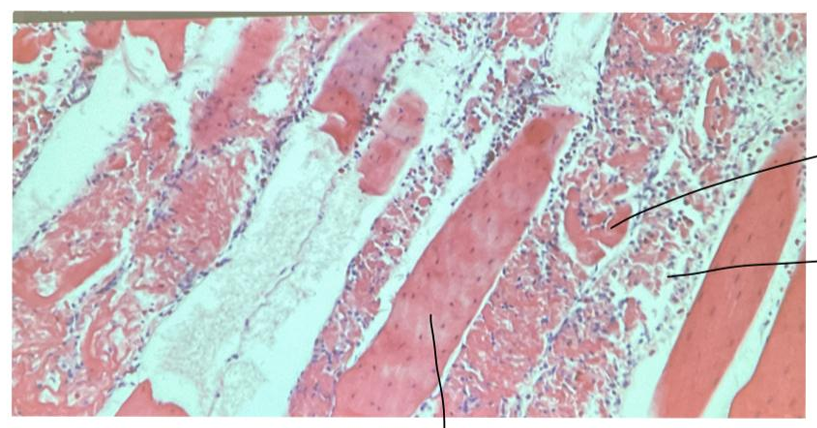

Dystrophia musculorum

this is?